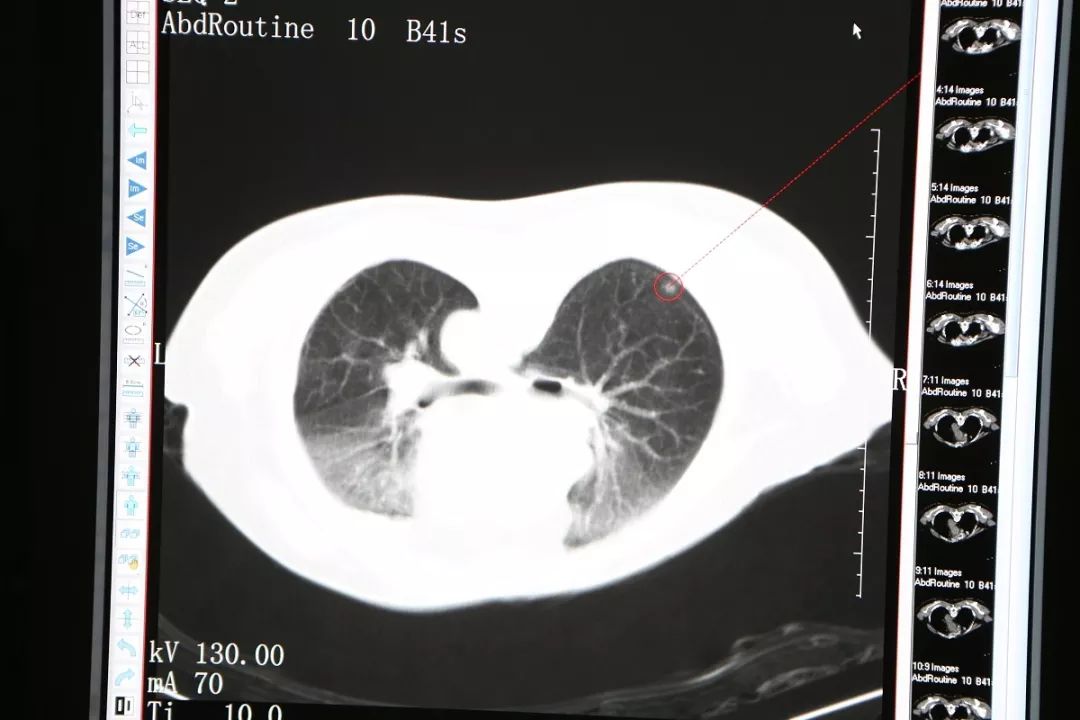

今年69岁的穆阿姨自退休以后就跟着儿子生活在新西兰,并取得了当地绿卡,偶尔返回厦门居住。今年7月她独自返回厦门小住,电视上“双肺毛玻璃”几个字眼触动了她,原来她在今年3月份的体检表上也有这几个字,第二天她去复查胸部CT显示“与2018-03-21CT比较:右肺下叶背段及左肺上叶磨玻璃结节较前相仿”,这时候她体内的磨玻璃影没有变化,她长舒了一口气,但医生建议她继续观察不要放松。到了10月份,她再次到当地医院做CT,发现磨玻璃影虽然没有变大,但是密度增加了,这时候她想起了在电视节目中看到的信息:“密度增加”就要引起关注,如今“密度增加”了表明病症在讯速进展。

穆阿姨来到复大肿瘤医院,迫不及待见了副院长牛立志教授与龙新安医生。龙新安介绍,“这位阿姨右肺下叶背段及左肺上叶磨玻璃结节较前相仿,新见右肺下叶炎性灶,初步诊断为双肺多发结节性质待定,传统手术双肺都有结节,要做两次楔形切除,对患者创伤较大,还有就是传统手术对许多的老年患者容易带来恐惧感。这种状况下只有冷冻消融才有可能把即将形成恶性肿瘤的组织物扼杀在萌芽状态。”得知明天要上手术台,穆阿姨坐卧不安,护士们看出了她的不安,主动与她聊天,她拉着护士的手说“真的很感谢你们,也很不好意思,耽误你们下班了”,护士却说“让你安心,是我们的职责,晚下班算得了什么,不下班都可以”,说着护士紧紧握住她的手,给她以心理安慰。

冷冻消融右肺背段结节

11月26日,穆阿姨被送至微创治疗室在CT引导静脉全麻下行右肺结节氩氦刀冷冻消融术,在实施静脉全麻后,术者将她摆成俯卧位,CT扫描以右肺背段近胸膜处结节为靶区,在CT引导下,用氩气超冷刀经穿刺点准确的穿刺到右肺结节,然后开始实施冷冻。术中通过CT扫描监测冷冻范围和有无并发症的发生,经过两个5分钟的冷冻循环后,CT扫描显示右肺的结节被成功的消融了。CT扫描见冰球覆盖靶区,复温后拔除超冷刀,包扎穿刺点,术中出血2ml,无手术标本,术后麻醉清醒,未诉不适,生命体征平稳。